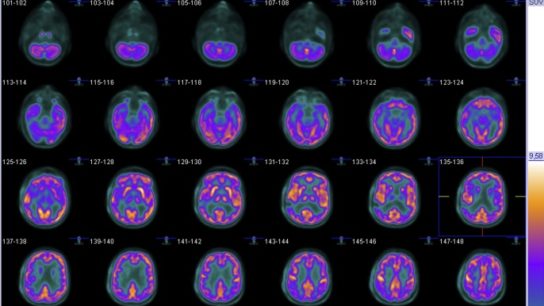

Neuroimaging could enable better classification of patients and provide information on affected brain regions.